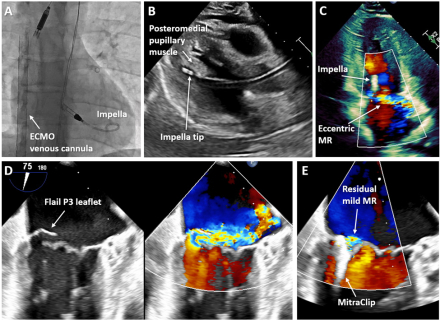

A 37-year-old male smoker presented with chest pain complicated by cardiac arrest due to ventricular fibrillation. Spontaneous circulation could not be restored, requiring veno-arterial extracorporeal membrane oxygenation (VA-ECMO). Coronary angiography revealed total occlusion of the proximal left anterior descending artery, which was successfully stented. Transfemoral Impella CP was placed for left ventricular venting under fluoroscopy (Panel A) with TTE showing no complications. In the intensive care unit, the Impella was advanced under TTE guidance; its tip was found to be positioned deep at the base of the posteromedial pupillary muscle without suction alarms or ventricular arrhythmias on the following day (Panel B). Several days later, TTE revealed new eccentric MR with hyperdynamic left ventricular motion (Panel C). The patient remained hemodynamically stable after VA-ECMO decannulation with Impella at P4. Following Impella removal, he developed repeated flash pulmonary edema despite aggressive fluid removal attributed to acute severe MR secondary to a flail P3 leaflet with ruptured chordae tendineae confirmed by transesophageal echocardiography (Panel D). Given the patient's poor surgical candidacy with a STS score of 13.2%, the team proceeded with mitral TEER, successfully reducing MR severity from severe to mild with a single NT Mitraclip® across the medial commissure (Panel E). His post-operative cardiac course was uneventful without recurrence of pulmonary edema.

Irreversible mechanical damage to the mitral valve apparatus caused by Impella placement and repositioning is a rare, potentially fatal complication requiring emergent intervention. Mitral TEER can be a viable salvage option for poor surgical candidates.